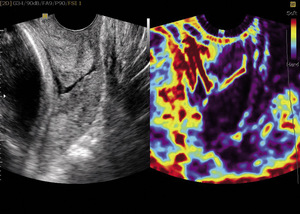

Pomysłem ośrodka gdańskiego było zastosowanie tej samej metody do oceny elastyczności szyjki macicy ciężarnej jako jednego z wykładników zbliżającego się porodu. Zastosowaliśmy badanie sondą pochwową w aparatach Samsung-Medison V10 i V20 z oprogramowaniem Elastoscan™. Uzyskane obrazy prezentują elastyczność tkanek w skali względnej. Przy zastosowaniu skali kolorów tęczy nr 2 tkanki najtwardsze obrazowane są jako fioletowe, mniej elastyczne jako niebieskie oraz dalej jako zielone i żółte, aby w kolorze czerwonym uwidocznić tkanki najbardziej podatne. Aby uzyskać obraz elastograficzny, potrzebny jest ruch. W elastografii położniczej ruch otaczających tkanek i naczyń krwionośnych szyjki jest wystarczający, aby uzyskać właściwe zobrazowanie.7-13

Na potrzeby analizy uzyskanych wyników w Klinice Położnictwa w Gdańsku opracowany został przez dr hab. med. Małgorzatę Świątkowską-Freund tzw. indeks elastografii (elastography index, EI), następnie opublikowany i zastosowany w naszych badaniach. Ta prosta pięciopunktowa skala (od 0 do 4 pkt) okazała się łatwa i skuteczna w zastosowaniu klinicznym.11,12

Z kolei w grupie ciężarnych w terminie porodu, które poddawane były indukcji porodu dożylnym wlewem kroplowym z oksytocyny, stwierdzono korelację między wartościami EI dla ujścia wewnętrznego a skuteczną indukcją porodu. Tutaj korelacja Pearsona była bardzo silna (r=0,71; p=0,0004). Wykazano również istotną różnicę między wartościami średnimi grupy, w której uzyskano efekt indukcji, a grupą z nieskuteczną indukcją w ciągu 8-godzinnego wlewu z oksytocyny (test t Studenta: p=0,024). Rycina 1 przedstawia graficznie stwierdzone różnice.